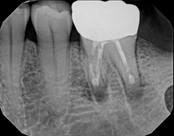

Non-surgical root canal treatment:

Before

After

6-month follow-upThe patient presented with mild pain, a cavity, and a broken filling was evident. After performing diagnostic testing, the diagnosis was: irreversible pulpitis, symptomatic periradicular periodontitis. Root canal therapy was done and the tooth healed well and is still functioning.